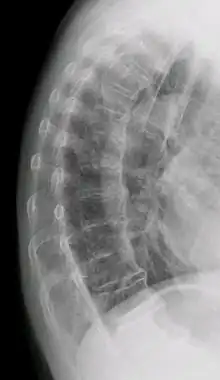

Confluent ossification of multiple contiguous vertebral bodies in diffuse idiopathic skeletal hyperostosis (DISH)

"Melted candle wax" appearance of calcification and ossification in diffuse idiopathic skeletal hyperostosis (DISH). Note the preponderance on the patient's left side (right side of image).